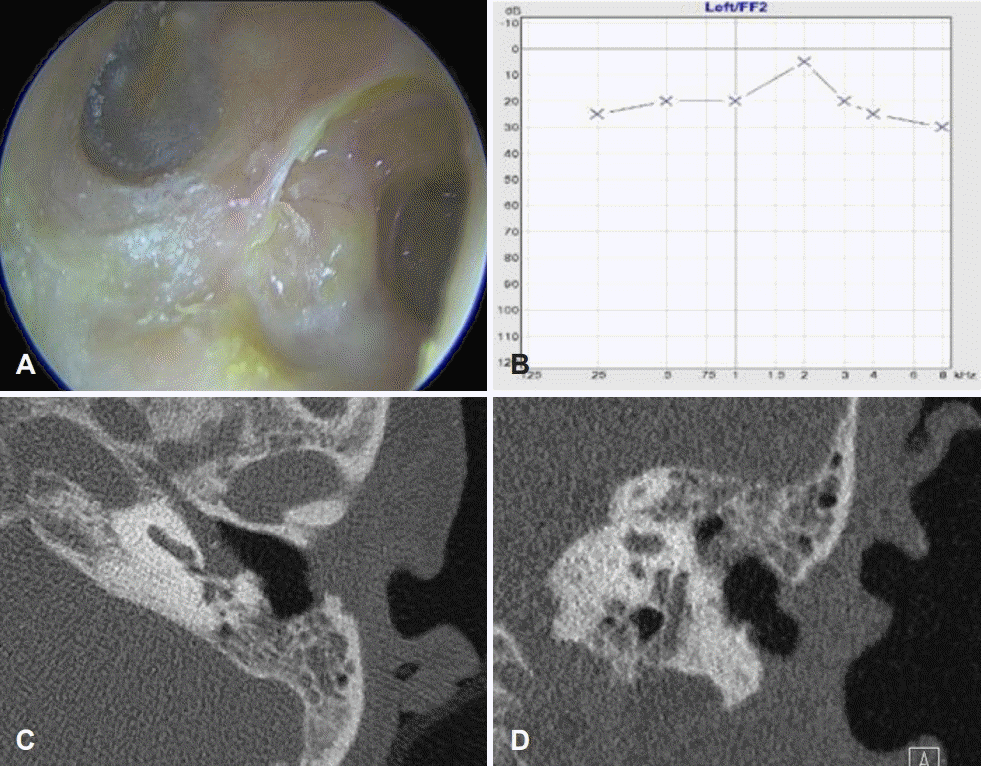

술후 24개월째 외래 진찰 소견상 골성 외이도 후벽은 잘 재건된 상태였고 청력도 잘 유지되고 있었다(Fig. 4A and B). 추적 측두골컴퓨터단층촬영 소견상에서도 외이도벽은 잘 재건되어 있었고 유양돌기 절제부위는 함기화 되어 있어 주기적인 외래추적 관찰 중이다(Fig. 4C and D).

Post-operative findiings of the patient. A and B: Transcanal endoscopic view in 15 months after operation shows the well-reconstructed posterior wall of bony external auditory canal (bEAC) (asterisk, A) and preserved hearing (B). C and D: Follow-up CT of the left temporal bone reveals reconstructed posterior EAC wall of bEAC with clearly mastoidectomized state.